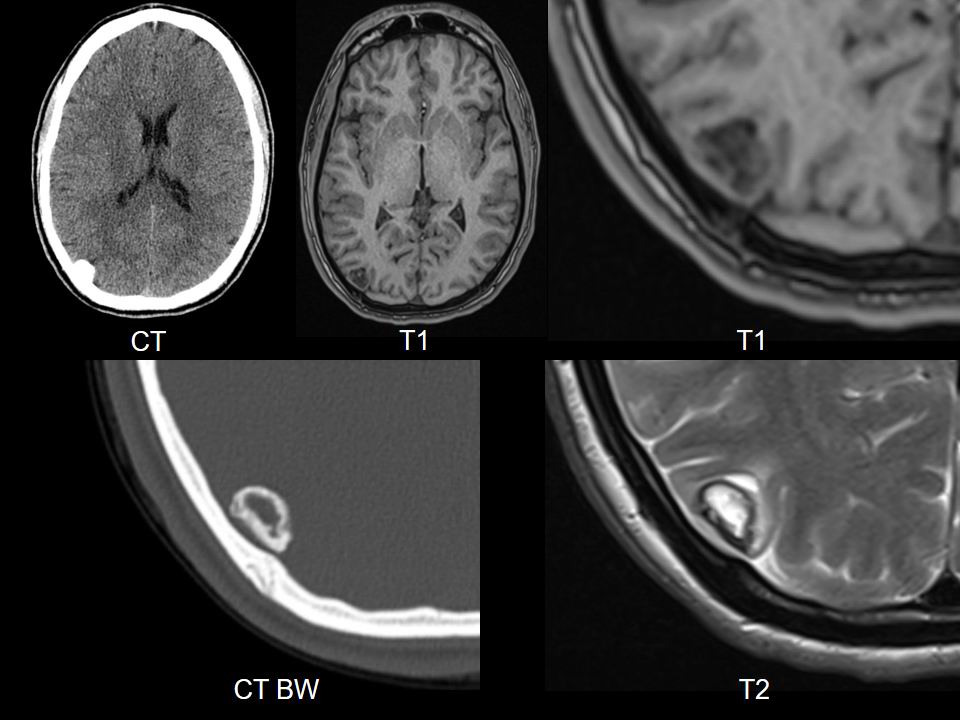

Representative_CT_+_MRI.jpg